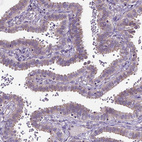

Immunohistochemical staining of human placenta shows moderate membranous/cytoplasmic positivity in trophoblastic cells.